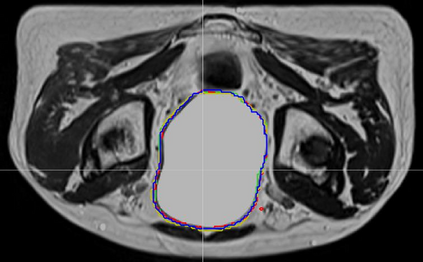

Direct automatic segmentation of objects from 3D medical imaging, such as magnetic resonance (MR) imaging, is challenging as it often involves accurately identifying a number of individual objects with complex geometries within a large volume under investigation. To address these challenges, most deep learning approaches typically enhance their learning capability by substantially increasing the complexity or the number of trainable parameters within their models. Consequently, these models generally require long inference time on standard workstations operating clinical MR systems and are restricted to high-performance computing hardware due to their large memory requirement. Further, to fit 3D dataset through these large models using limited computer memory, trade-off techniques such as patch-wise training are often used which sacrifice the fine-scale geometric information from input images which could be clinically significant for diagnostic purposes. To address these challenges, we present a compact convolutional neural network with a shallow memory footprint to efficiently reduce the number of model parameters required for state-of-art performance. This is critical for practical employment as most clinical environments only have low-end hardware with limited computing power and memory. The proposed network can maintain data integrity by directly processing large full-size 3D input volumes with no patches required and significantly reduces the computational time required for both training and inference. We also propose a novel loss function with extra shape constraint to improve the accuracy for imbalanced classes in 3D MR images.

翻译:3D医学成像的物体,如磁共振成像(MR)成像的直接自动分离,具有挑战性,因为往往需要精确地确定大量调查中大量存在复杂地理不对称的单个物体。为了应对这些挑战,大多数深层学习方法通常会大大提高其模型内可训练参数的复杂性或数量,从而提高其学习能力。因此,这些模型一般需要在运行临床MR系统的标准工作站上花很长的推断时间,并限于高性能的计算机硬件,因为它们的记忆要求很大。此外,要在这些大型模型中安装3D数据集,还要利用有限的计算机记忆,经常使用交换技术,例如补对称培训等,以牺牲从对诊断目的具有临床重要性的投入图像中获得的精细比例的几何地理信息。为了应对这些挑战,我们提出一个具有浅度记忆足迹的银色网络,以有效减少为状态性能所需的模型参数数量。这对于实际就业至关重要,因为大多数临床环境只有低端硬件,计算机功能和记忆有限。拟议的网络可以通过直接处理全尺寸三维化技术来保持数据的完整性,直接处理全尺寸的全尺寸三维的图像,从而大幅改进所需的超度变压的磁度计算。